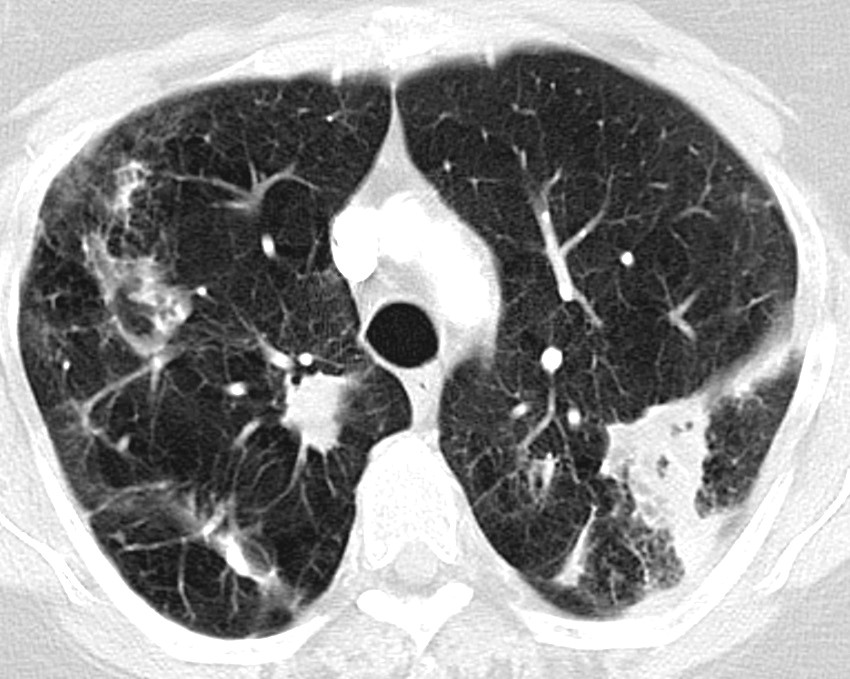

When NTM pulmonary disease is suspected, the patient should undergo a CT thorax. The two most common radiological presentations are the fibrocavitary and nodular bronchiectasis forms (23, 24). The fibrocavitary form has cavitary lesions, most frequently in the upper lobes, with radiological findings that resemble tuberculosis (Fig. 1). This form often has a more aggressive course, and is seen most frequently in elderly men who smoke or have another pulmonary disease, such as chronic obstructive pulmonary disease, or have had tuberculosis. The nodular bronchiectasis form is characterised by multifocal bronchiectasis and small nodules, most frequently in non-smoking, elderly women. This form is also over-represented in patients with a low body mass index, scoliosis, pectus excavatum, mitral prolapse, and in tall persons (17, 19).